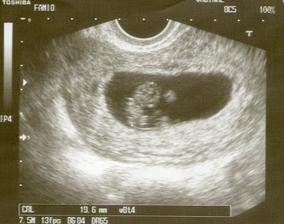

♥ 4.2.2009♥ Menší poplach, maminka trošičku špinila, takže neplanovaná kontrola a 2. UTZ. Ale vše je ok, srdíčko krásně tluče a brouček měl otevřenou pusinku 🙂